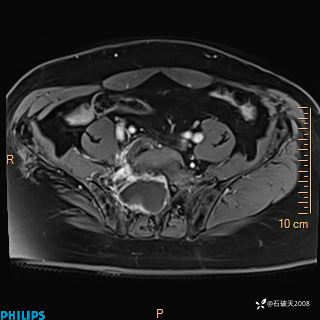

2023年3月份MRI影像

增强轴位